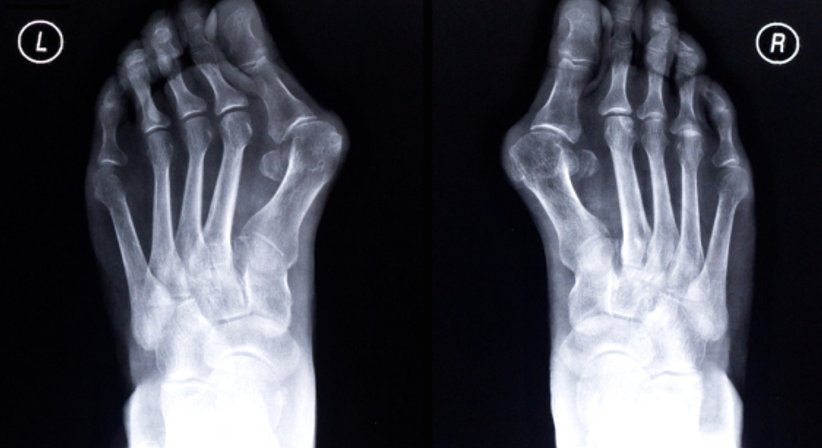

Beim Hallux valgus handelt es sich um eine Deformierung des Großzehenballens (Fehlstellung der Großzehe im Grundgelenk nach außen hin), die zumeist mit einer abnormen Spreizung im Bereich vom Mittelfuß einhergeht.

Der Hallux valgus ist die häufigste Fehlstellung/Deformität im Vorfußbereich, die Großzehe verändert ihre natürliche Stellung und winkelt sich allmählich in Richtung der anderen Zehen ab. In vielen Fällen verdrängt der große Zeh die anderen Zehen auch aus ihrer natürlichen Position; aufgrund der Schiefstellung beginnt sich der Ballenbereich am Innenfuß vorzuwölben und nach einiger Zeit wird die für den Hallux valgus charakteristische Beule sicht- und tastbar. In schweren Fällen kommt es durch die Schiefstellung zu einer chronischen Überlastung der benachbarten Zehen und Gelenke sowie des Mittelfußknochens.